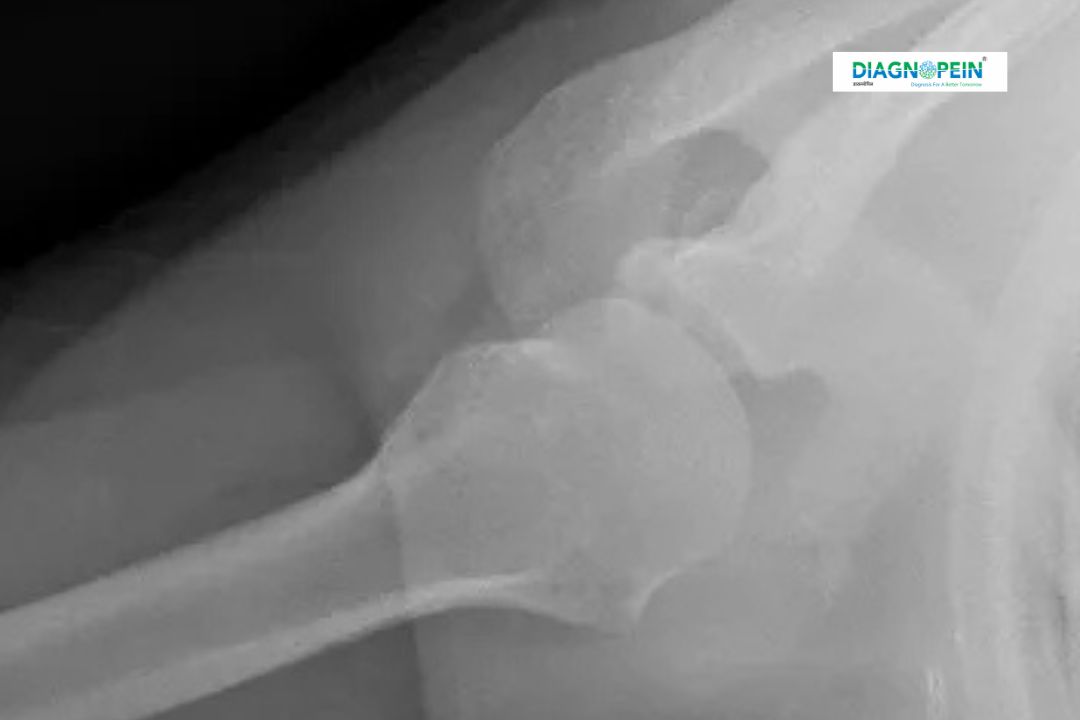

X-RAY SHOULDER AXIAL is a specialized radiographic imaging technique used to obtain a clear axial (top-down) view of the shoulder joint, particularly the relationship between the humeral head and the glenoid cavity. This view plays a crucial role in accurately assessing shoulder joint alignment, injuries, and structural abnormalities that may not be visible on standard AP or lateral shoulder X-rays.

The shoulder joint is one of the most mobile joints in the human body, making it highly susceptible to injuries such as dislocations, fractures, and degenerative conditions. X-RAY SHOULDER AXIAL is particularly important because it provides a direct view of the joint space, allowing doctors to evaluate the exact position of the humeral head relative to the socket.

This imaging view is essential for detecting anterior or posterior shoulder dislocations, assessing joint congruency, and identifying subtle fractures of the glenoid rim. Orthopedic specialists often rely on X-RAY SHOULDER AXIAL imaging to plan appropriate treatment strategies, especially after trauma or sports injuries.